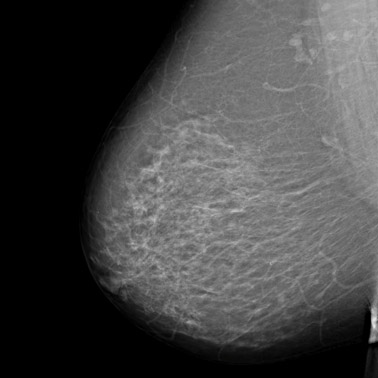

MRT zur Diagnostik der weiblichen Brust (Mammadiagnostik, Mamma-MRT)

Eine Kernspintomographie der Brust wird eingesetzt, wenn die Tastuntersuchung, Mammographie, Sonographie oder eine Biopsie keinen eindeutigen Befund ergeben haben und man mit Hilfe einer weitere Untersuchung Brustkrebs auszuschließen will.

Kernspintomographie (MRT, Magnetresonanztomographie): Die Mamma-MRT, ein Untersuchungsverfahren, das im Gegensatz zur Röntgentechnik mit Magnetfeldern arbeitet, findet bei uns in der Brustkrebsdiagnostik ebenfalls Anwendung. Es ist in der Regel dann erforderlich, wenn die vorhergehende Untersuchung per Mammographie oder Sonographie keinen klaren Befund ergeben hat.

Brusttumor 1

Brusttumor 2